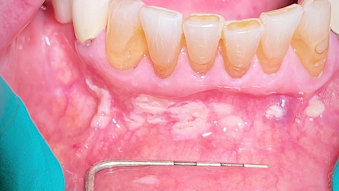

Diagnostic Imaging Techniques In Oral Diseases Springerlink